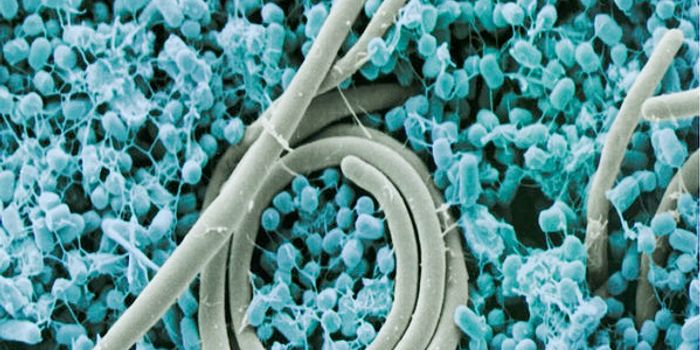

MAR 16, 2015MicrobiologyTargeting deadly, drug-resistant bacteria poses a serious challenge to researchers looking for antibiotics that can kill ...